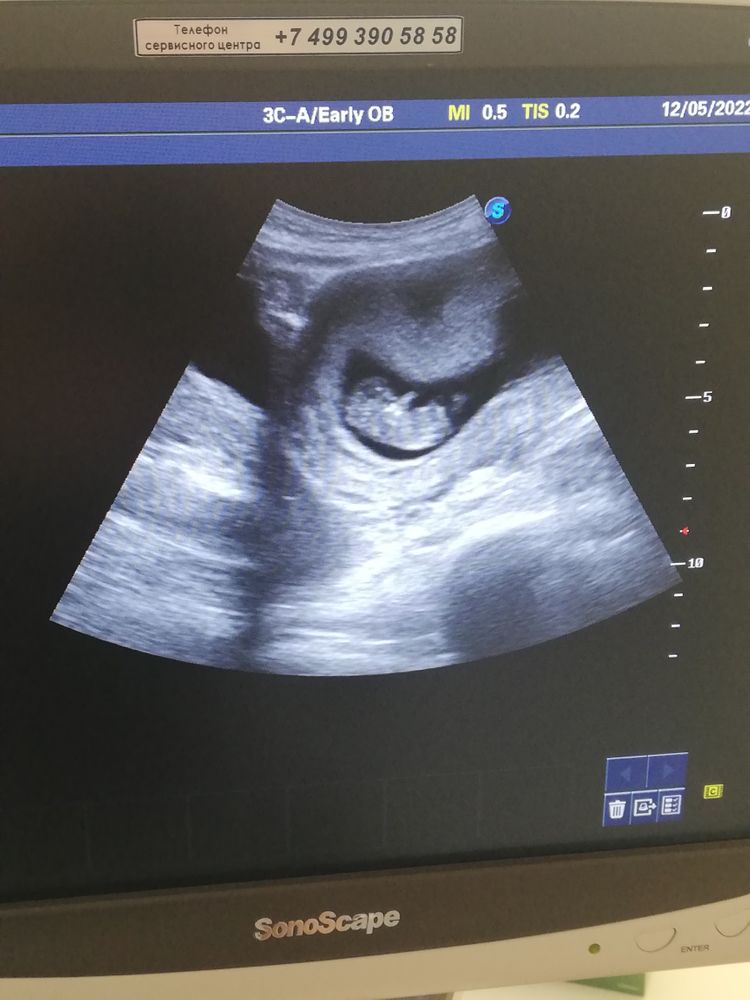

Нам 10 недель 😍

Сегодня было моё первое узи по беременности 😍 Ой девочки, аж слёзы на глазах появились как я увидела маленькую кроху 😍😍😍 Мы уже 3 см, сердцебиение 174. Я правда этому немного удивилась, так как думала что у меня 9 недель, считала по календарю в приложении, по дате последних месячных. Вот завтра в жк к врачу, на учёт. Вообщем, я очень рада ❤️